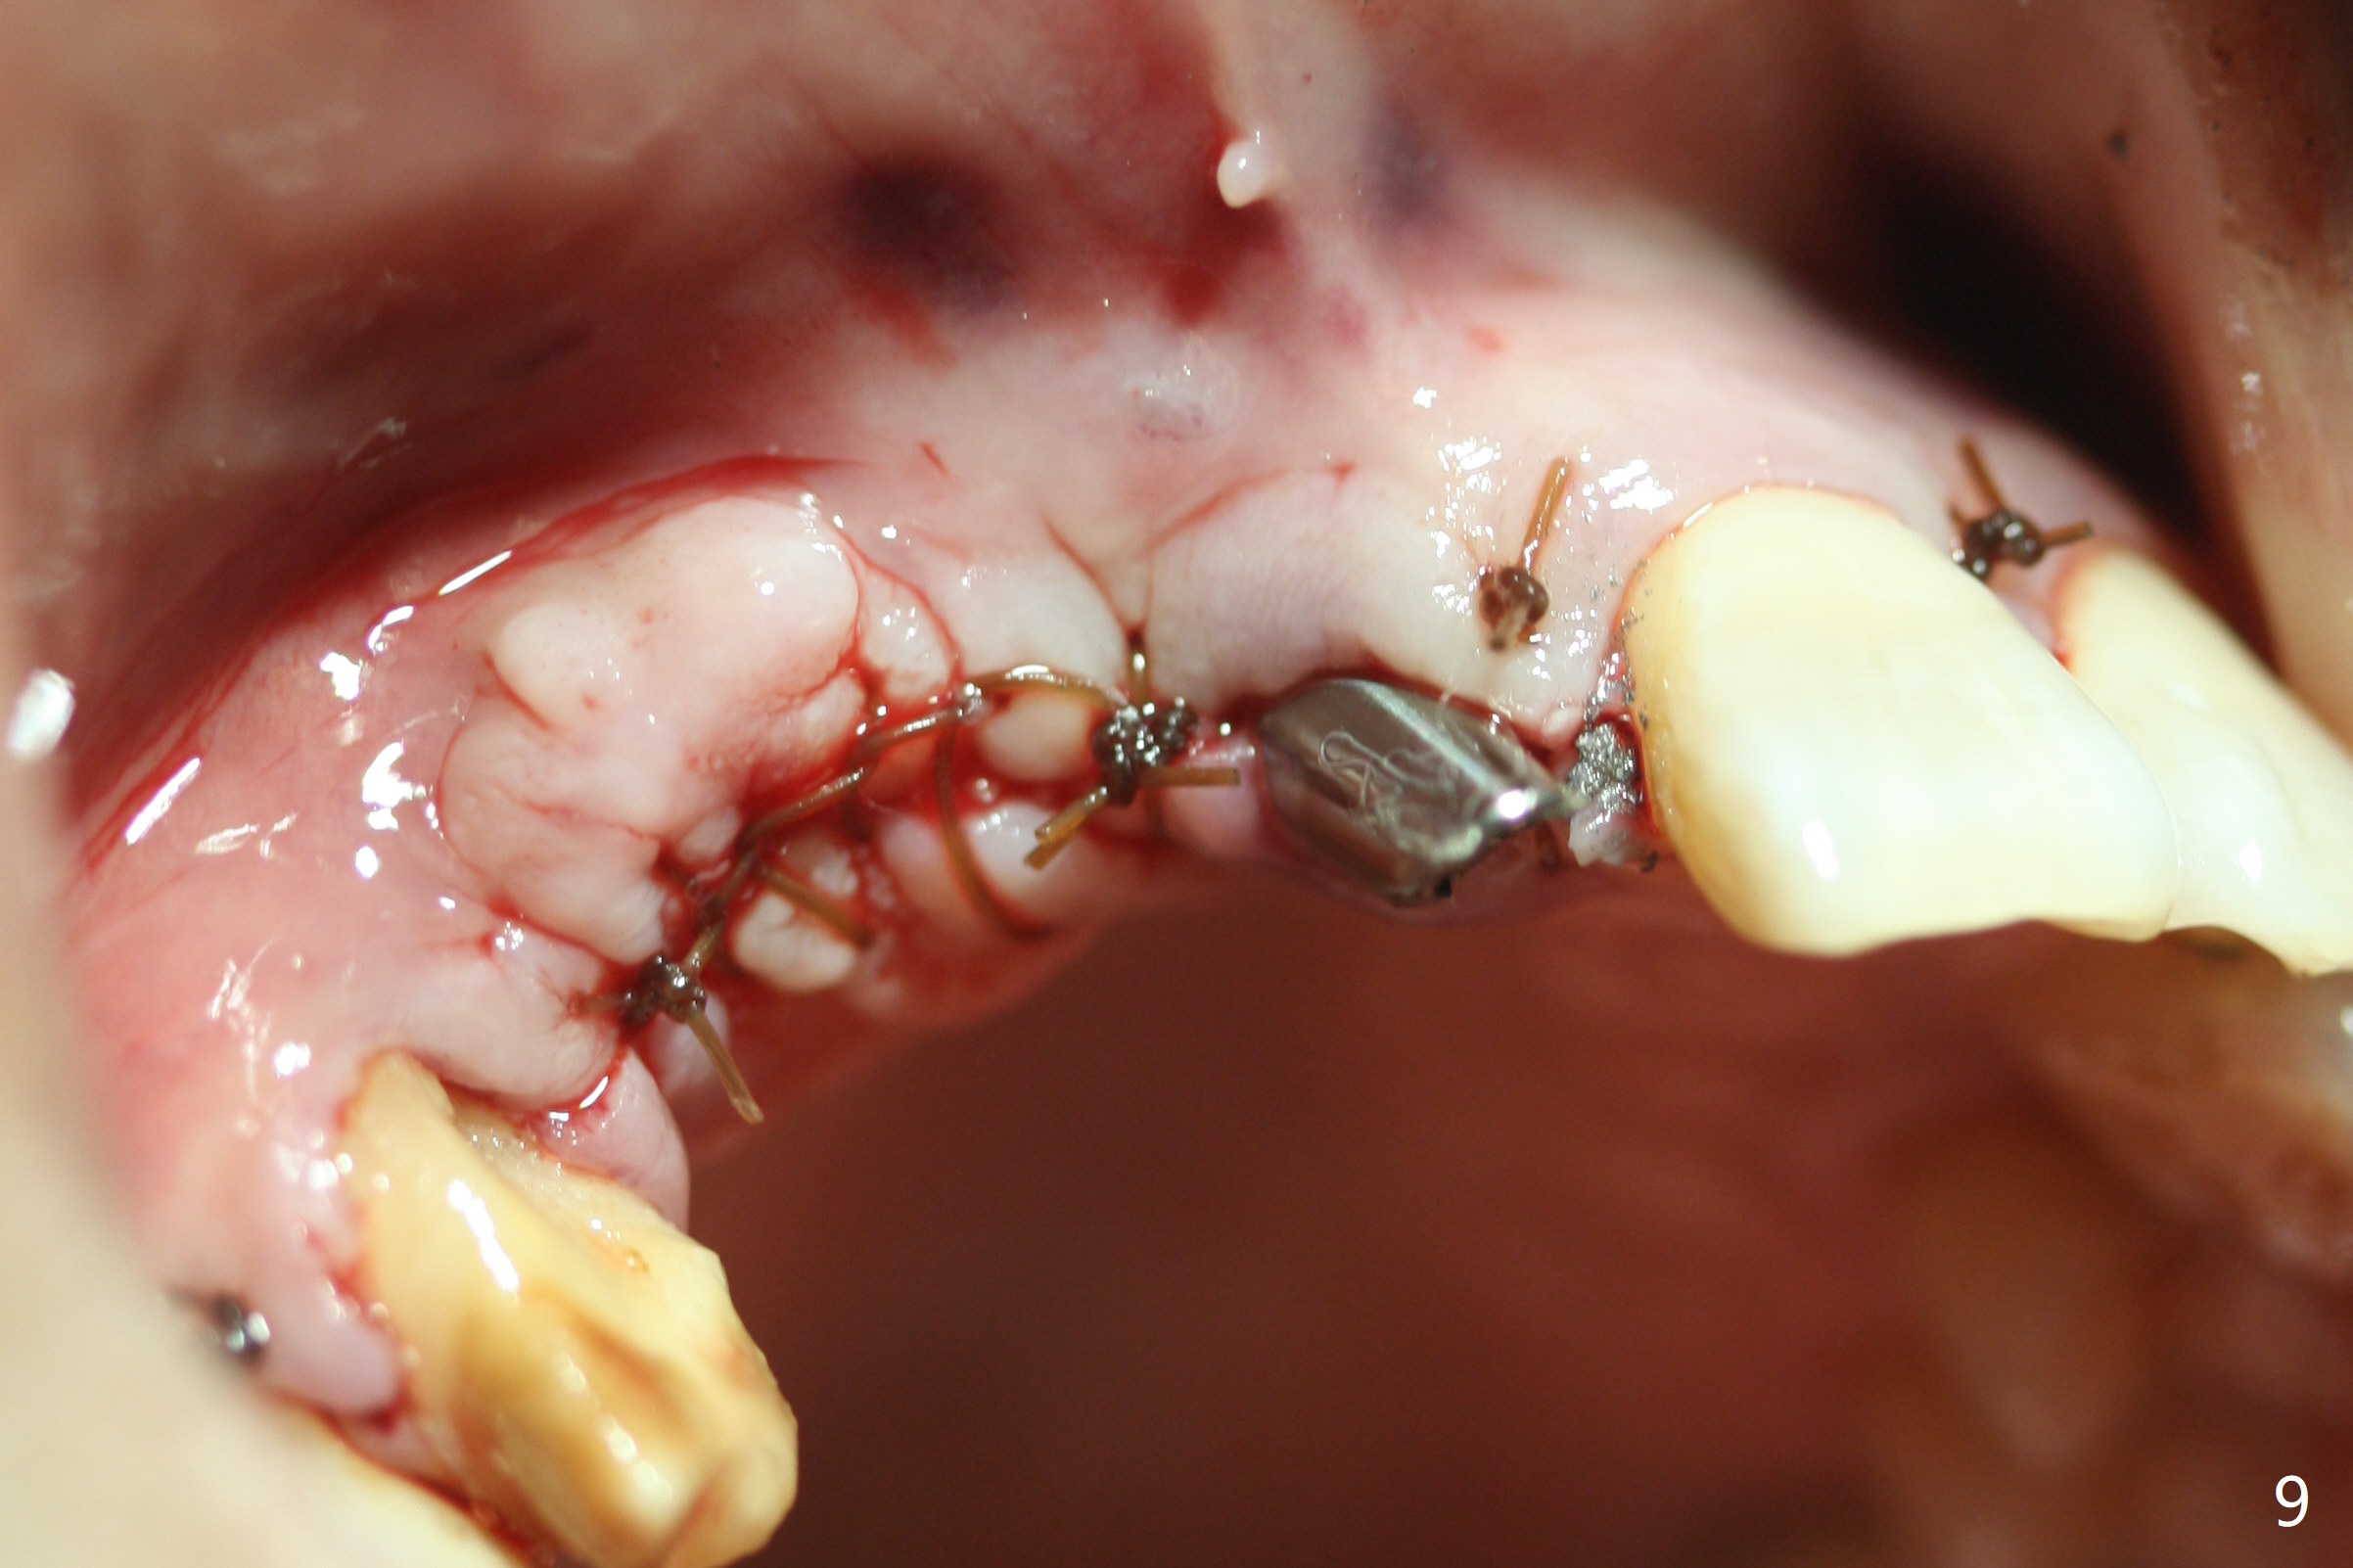

Eleven months post immediate implantation, the implant at #8 (4.5x16 mm, better smaller) is found to have thread exposure buccally (Fig.1) and distally (Fig.2). Immediately post implant removal, a 5x10 mm one is placed equi- or subcrestally distobuccally (Fig.3,4 (to prevent periimplantitis)). It is turned 4 more times later to make sure slightly supracrestally palatally, since the palatal crest is the lowest. After placement of sticky bone palatally, a 4.5(2) mm mill abutment is placed (17 mm long, Fig.5,6). The buccal flap is raised until the anterior nasal (Fig.5 N) foramen. After severing the periosteum and placement of 2 of 8 mm tenting screws (Fig.7), sticky bone (Vanilla allograft/Osteogen; block graft denies) is applied at #6 and 7 sites (Fig.8). Following palatal flap separation, the wound is closed in an apparent tension free manner (Fig.9). Periodontal dressing is applied. After wound healing, lab-fabricated provisional is delivered.